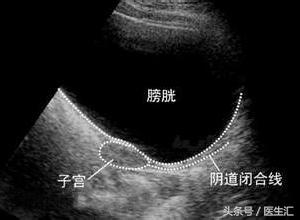

患者因为雌激素很低,子宫没有发育,B超不能准确判断是否为始基子宫。

始基子宫为双侧副中肾管融合后不久即停止发育,子宫极小,多数无宫腔或为实体肌性子宫,无子宫内膜,没有功能,再补充雌激素也长不大;幼稚子宫为双侧副中肾管融合形成子宫后发育停止所致,有子宫内膜。

子宫和人是一样的,人要靠吃饭长大,子宫要靠吃雌激素长大,患者为低雌激素性闭经,雌激素非常低,第二性征没有发育,B超子宫偏小,可能为幼稚子宫,是因为缺乏雌激素导致的,而低促性腺激素性闭经患者同时伴有子宫异常比较少见。

当补充雌激素后,患者第二性征发育,子宫也逐渐长大,当补充孕激素时,能撤退出血,表明这个子宫是有功能的,在当时未补充雌激素时为幼稚子宫;如果当补充雌激素后,患者第二性征发育,但子宫仍未长大,则为无功能的子宫,才称为始基子宫。